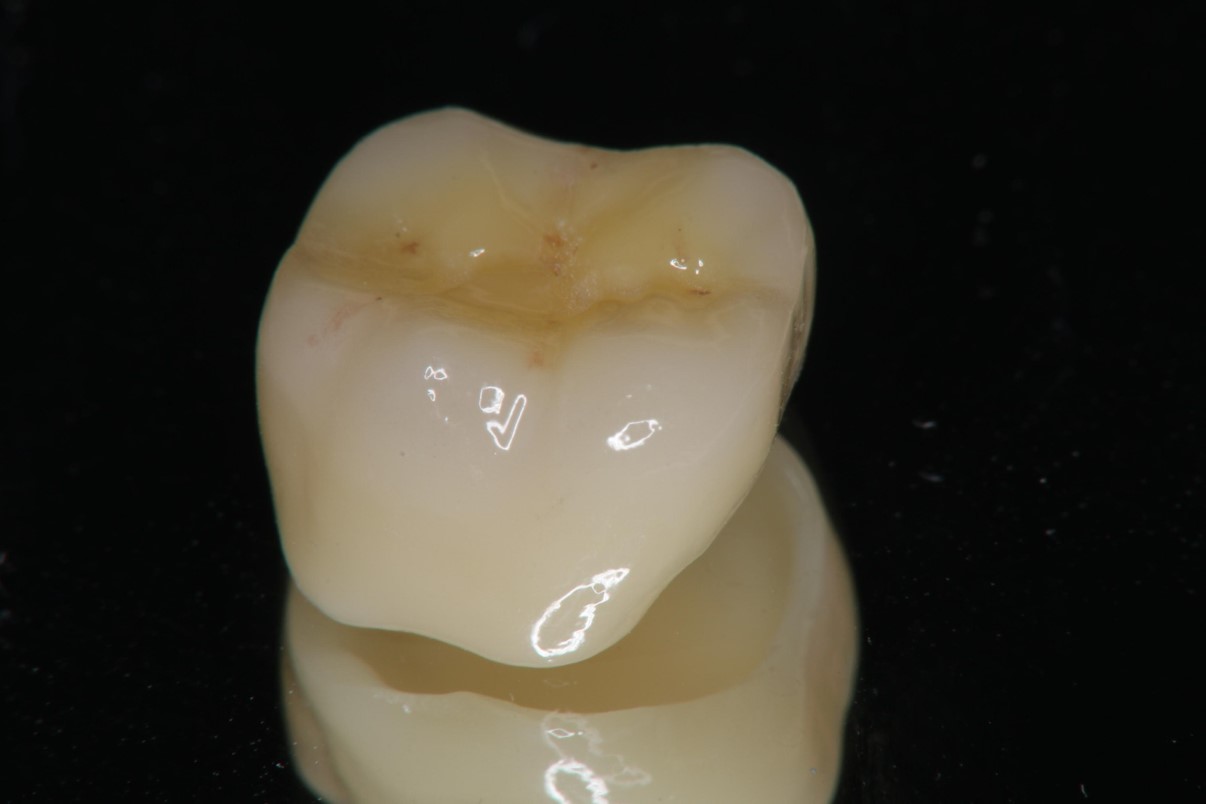

全鋯冠